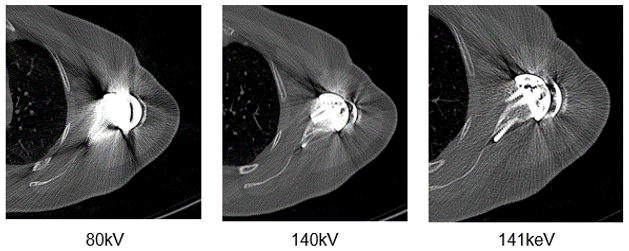

It is also possible to adapt the kV values used based on the visualized structure or to use dual-energy protocols. Notice the difference in streaking in these three images.

Let’s look at the differences in these four images taken at different dual energy levels. Compare the streak artifacts with the 80kV, 140 kV, the mixed acquisition of 140kV and 80 kV and the last at 140 keV.